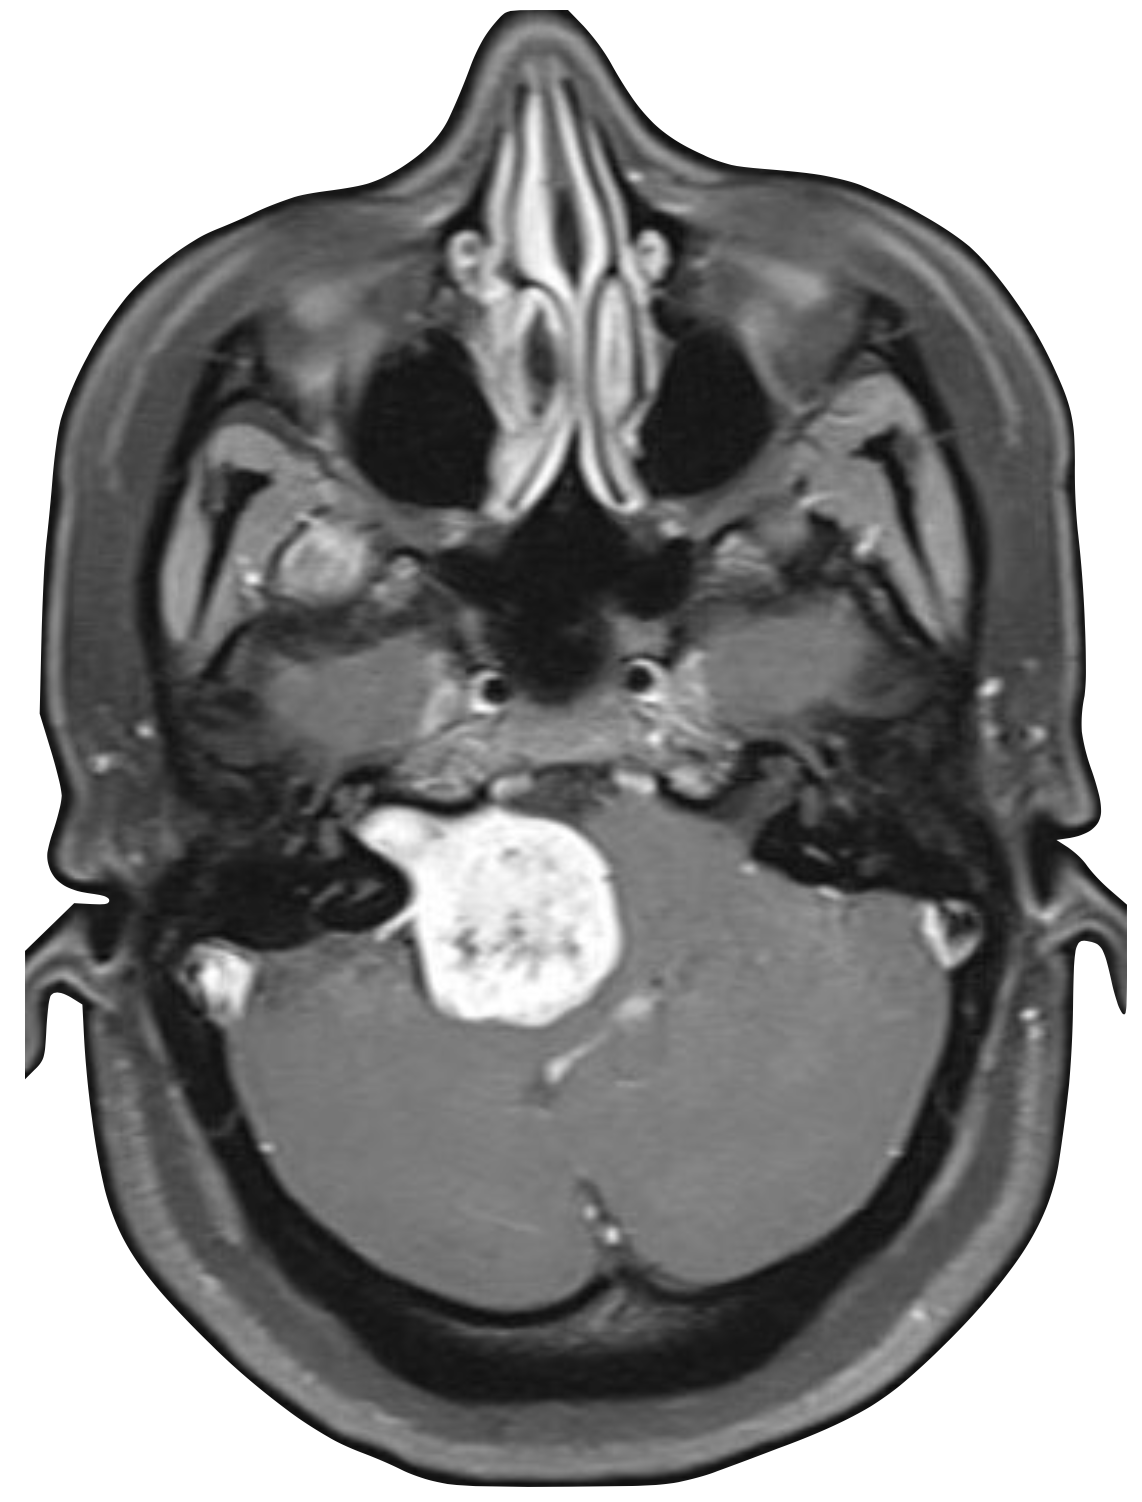

Advanced otology encompasses complex ear and skull base conditions requiring specialized surgical care. We offer cochlear implants and bone conduction implants for hearing loss, treat acoustic neuroma and temporal bone tumors, and perform stapes surgery for otosclerosis. Our team also manages cholesteatoma, superior canal dehiscence, and other advanced ear conditions. Select a topic below to learn more.